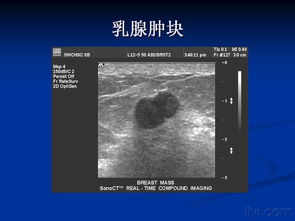

超聲對于病變的解剖部位或器官組織定位的診斷有比較高度的準(zhǔn)確性,如心臟的瓣膜、肝臟的外葉上段,腎的下級或者上級等等。病變特征的診斷區(qū)分為彌漫性或局限性,囊性、實(shí)性或混合型。

超聲對病變物理性質(zhì)的判斷通常也是非常準(zhǔn)確的。良性或惡性的診斷,只有在具有高度特異性的超聲表現(xiàn)的情況下,通過綜合判斷超聲才可以提示肯定而明確的診斷,如膽囊結(jié)石、死胎、肝囊腫等等。

必須強(qiáng)調(diào)的是超聲影像診斷不是病理組織學(xué)的診斷,由于大多數(shù)疾病的超聲表現(xiàn)是非特異性的,只能結(jié)合病史綜合分析,提示某一或某些疾病的可能性,所以在報(bào)告單中可以出現(xiàn)如甲狀腺左葉低回聲結(jié)節(jié),性質(zhì)待定這樣的結(jié)論。這時(shí)大夫會提出進(jìn)一步的診斷建議,如穿刺活檢、CT掃查或者是甲狀腺功能檢查等等。